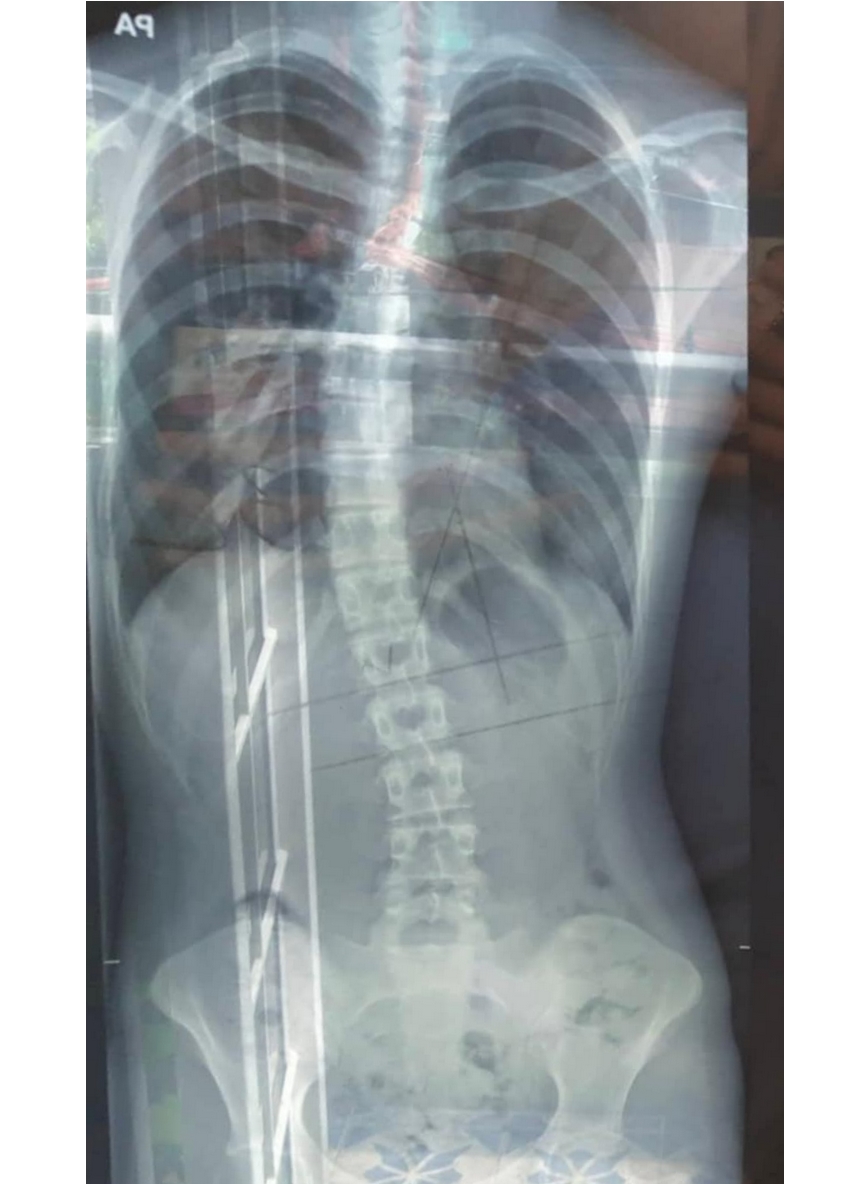

X-ray showing a curved spine before scoliosis treatment, highlighting spinal misalignment.X-ray showing a straighter spine after posture aid treatment, with improved spinal alignment.